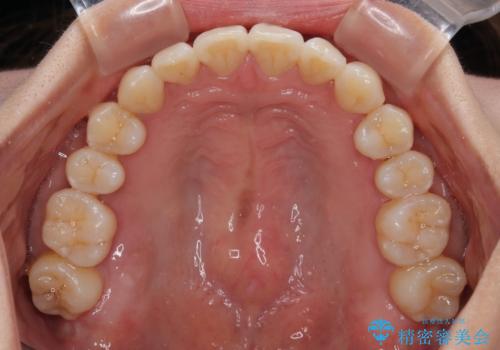

【モニター】上顎前突と奥歯の鋏状咬合 補助装置を用いたインビザライン矯正治療

- 前歯の歯列不正と奥歯の咬みにくさを気にして来院された患者様です。

インビザラインでの矯正治療を希望されていましたが、奥歯の咬み合わせがインビザライン単独では改善困難と判断されたので、補助装置を併用することとしました。

上顎最後臼歯は極端に外側を向いており、下顎骨に対して上顎骨が前方に位置していたため、補助装置により最後臼歯を一気に内側に引き込むとともに、上顎臼歯を後方移動させ、奥歯の咬み合わせが改善した後に、上下インビザラインにより歯列全体を整えていくこととしました。

奥歯の咬み合わせを事前に望ましい位置に改善したことで、インビザライン単独では改善が最も困難な状況を排除することができ、非常に理想的な仕上がりとなりました。